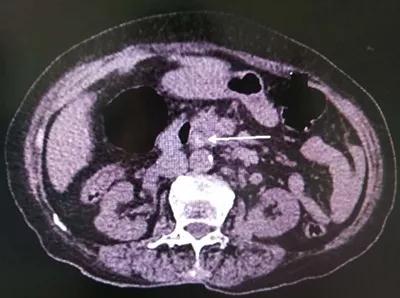

5分钟后,杨林副主任便赶到急诊科,这时腹部CT结果已经出来:胆总管多发结石伴胆道系统扩张,胆囊切除术后。

综合患者病情,杨林副主任认为其是典型的胆总管结石伴急性梗阻化脓性胆管炎(AOSC),如不立刻进行胆汁引流,会出现严重的并发症甚至危及生命。考虑到患者高龄,且基础疾病复杂,建议首先行ERCP引流胆汁,但因去年曾在外院做过此手术却没有解决病根,所以家人坚决拒绝内镜治疗(ERCP)。没办法,只有手术一条途径可走了…